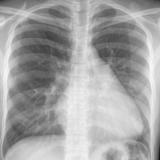

ASD 1 PA